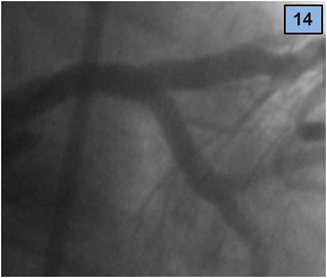

Figure 14 Final result, RAO view.